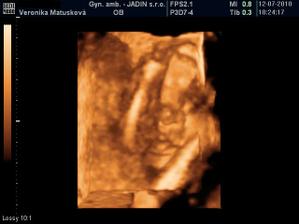

Adamko - 3D/4D

No tot vidno, že je náš syn, sa hanbil a hanbil až sa ukazovať nechcel....ale niekedy sa to podarilo, aj ked to nie je nejaká sláva. Pán doktor nám potvrdil chlapčeka, tak sme radi, vajká ukazoval ako len vedel len toho pipíka stále schovával. Ale je to za nami, pán doktor nás pekne popísal čo je kde, poodmeral nás a povedal, že je všetko v poriadku.